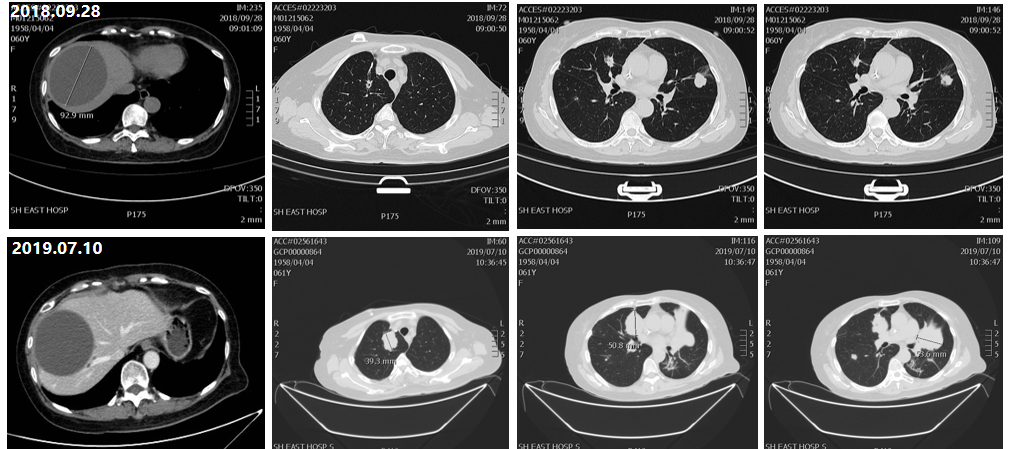

一线治疗(2018年6月10日——2019年7月10日)

治疗评估:2018年6月10日,患者双肺部再次出现多发病灶,患者起初拒绝化疗,在当地医生及患者家属强烈建议下,患者接受化疗治疗;

治疗方案:行贝伐珠单抗联合FOLFORI(伊立替康+氟尿嘧啶)方案8周期,后行贝伐联合伊立替康维持治疗;

疗效评估:2019年7月患者双肺病灶及肝脏病灶出现增大,提示疾病进展(PD);

图1 一线治疗CT影像对比